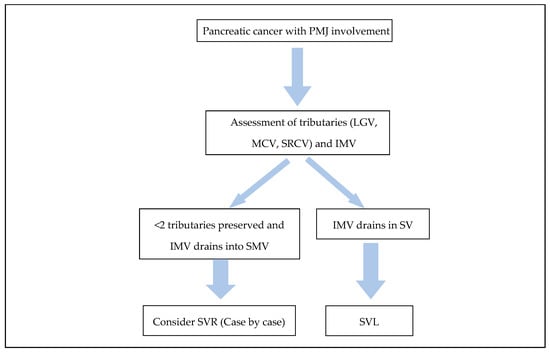

Necessity and Reconstruction Methods of Splenic Vein After Resection of the Portomesenteric Junction During Resections for Pancreatic Cancer

Curr. Oncol. 2025, 32(6), 316; https://doi.org/10.3390/curroncol32060316 - 30 May 2025

Pancreatic cancer involving the porto-mesenteric junction (PMJ) represents a challenge to pancreatic surgeons. Restoring mesenteric venous drainage is an essential component of vascular reconstruction after tumour resection. In contrast, management of the splenic venous drainage can involve the ligation or reconstruction of the

Pancreatic cancer involving the porto-mesenteric junction (PMJ) represents a challenge to pancreatic surgeons. Restoring mesenteric venous drainage is an essential component of vascular reconstruction after tumour resection. In contrast, management of the splenic venous drainage can involve the ligation or reconstruction of the splenic vein (SV). Evidence suggests that splenic vein ligation (SVL) is commonly associated with sinistral portal hypertension (SPH), especially if multiple venous tributaries were divided to facilitate resection. Although the association between SVL and SPH is well documented, the risk of symptomatic SPH is not widely reported, presumably due to the low incidence and poor survival of pancreatic cancer patients. Splenic vein reconstruction (SVR) has been proposed to decrease the risk of SPH but is fraught with technical complexity and increased morbidity. Moreover, SVR does not guarantee the prevention of SPH, as patency rates vary and associated hemodynamic changes are unpredictable. Patient selection and the surgical expertise available can guide SV intraoperative management, taking into consideration the risks and benefits associated with each approach. A comprehensive review of the current literature highlighting the incidence and clinical impact of SPH after the resection of pancreatic cancer involving the PMJ is presented.